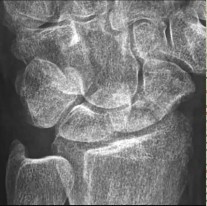

- الأشعة السينية (X-rays): هي الخطوة الأولى في تقييم الكسور، الخلوع، وتغيرات التهاب المفاصل. تساعد في تحديد مدى تدهور العظام والمسافات المفصلية. على سبيل المثال، تُظهر صور الأشعة السينية كسور السلاميات

أو كسور قاعدة العظم المشطي الخامس